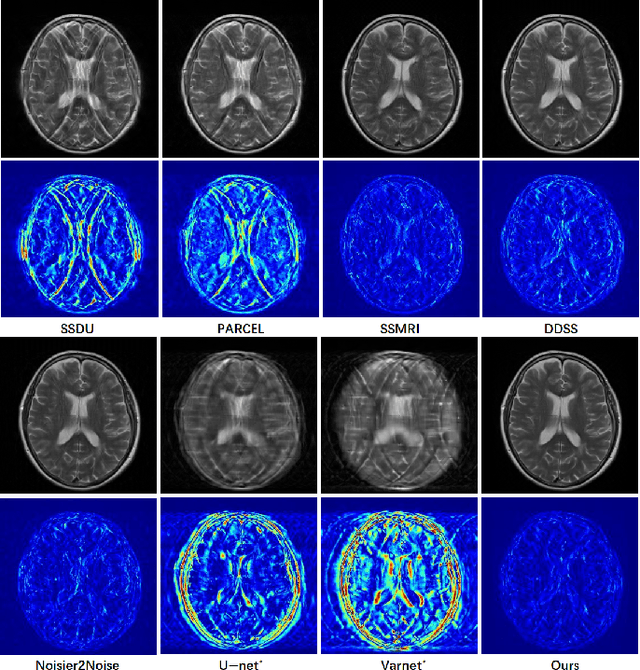

Abstract:Magnetic Resonance Imaging (MRI) is widely used in clinical practice, but suffered from prolonged acquisition time. Although deep learning methods have been proposed to accelerate acquisition and demonstrate promising performance, they rely on high-quality fully-sampled datasets for training in a supervised manner. However, such datasets are time-consuming and expensive-to-collect, which constrains their broader applications. On the other hand, self-supervised methods offer an alternative by enabling learning from under-sampled data alone, but most existing methods rely on further partitioned under-sampled k-space data as model's input for training, resulting in a loss of valuable information. Additionally, their models have not fully incorporated image priors, leading to degraded reconstruction performance. In this paper, we propose a novel re-visible dual-domain self-supervised deep unfolding network to address these issues when only under-sampled datasets are available. Specifically, by incorporating re-visible dual-domain loss, all under-sampled k-space data are utilized during training to mitigate information loss caused by further partitioning. This design enables the model to implicitly adapt to all under-sampled k-space data as input. Additionally, we design a deep unfolding network based on Chambolle and Pock Proximal Point Algorithm (DUN-CP-PPA) to achieve end-to-end reconstruction, incorporating imaging physics and image priors to guide the reconstruction process. By employing a Spatial-Frequency Feature Extraction (SFFE) block to capture global and local feature representation, we enhance the model's efficiency to learn comprehensive image priors. Experiments conducted on the fastMRI and IXI datasets demonstrate that our method significantly outperforms state-of-the-art approaches in terms of reconstruction performance.